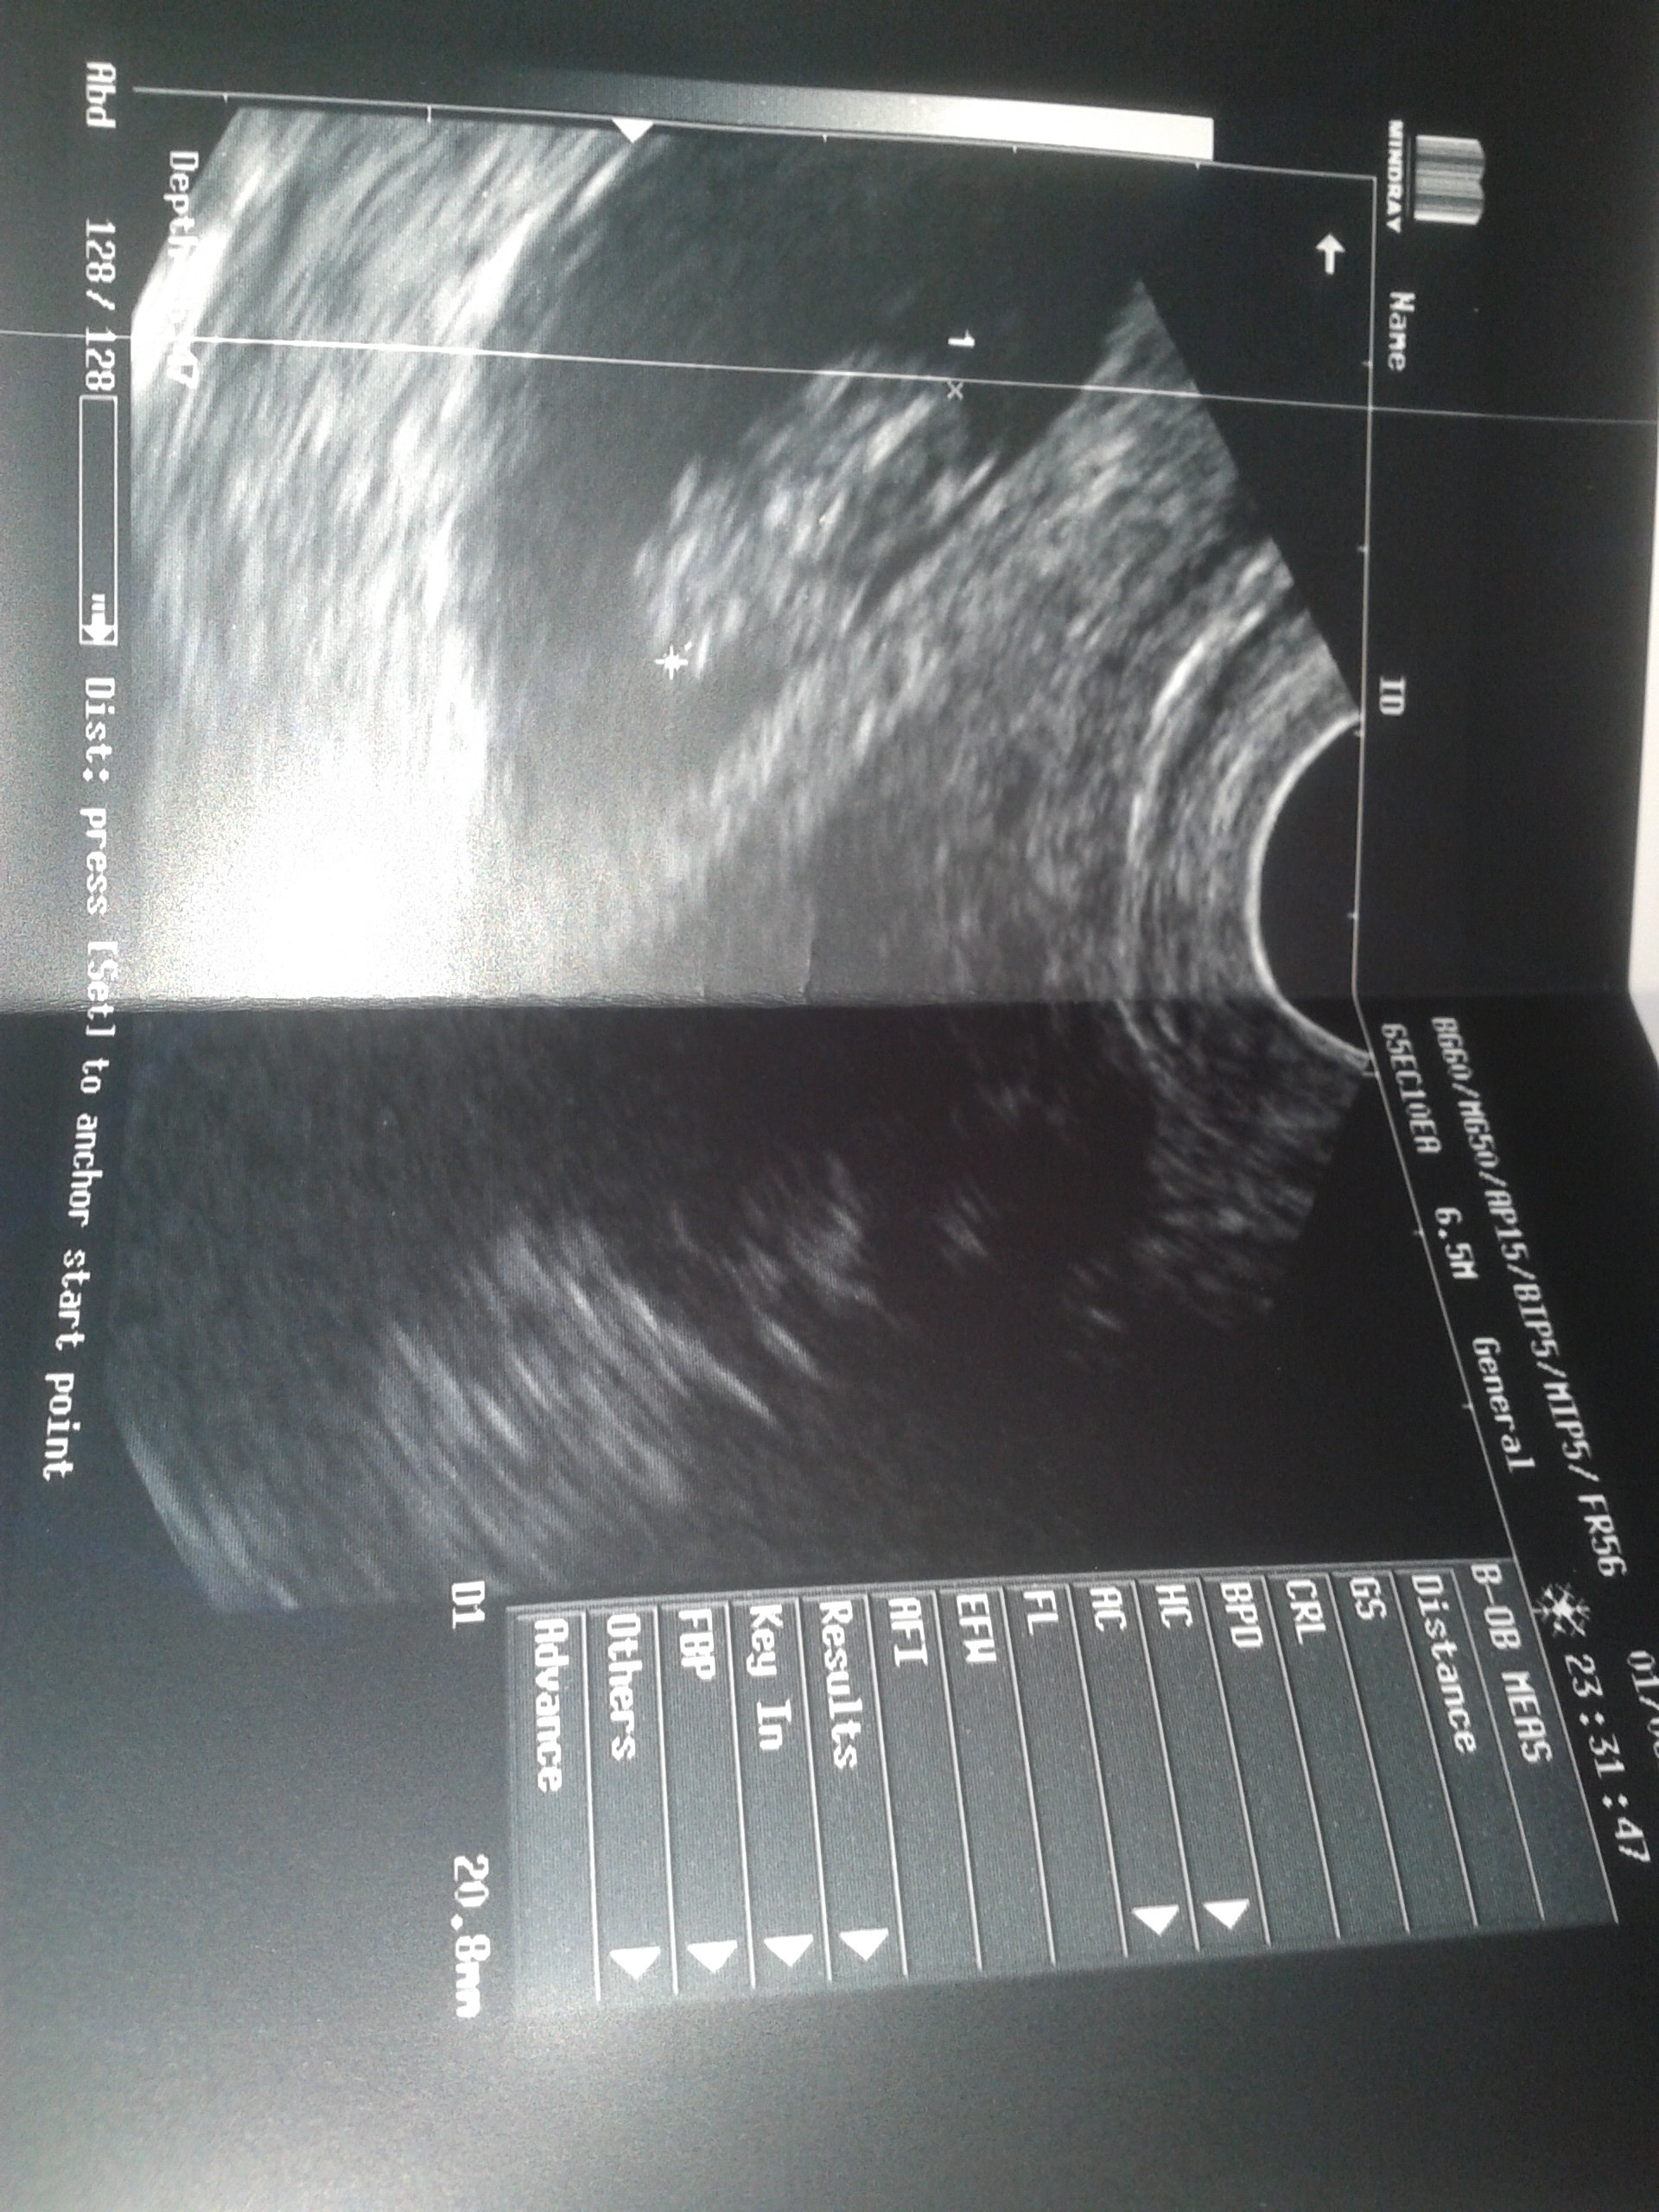

Dziewczyny jestem po usg .. Wszystko jest niby okey z terminem jakoś dziwnie.

Bo tak z usg wychodzi na 6.01.2017

ale od ostatniego okresu wychodzi 19.12.2016.

Ale serduszko widac .. A zobaczyłam dzisiaj jak się rusza ! Ginekolozka mi powiedziała nawet niech Pani patrzy już kopie :D

Az mi łzy w oczach staneły :) To 9 tydzien i 1 d :) Doodaje zdjecie cos tam widac

Załączniki

• 20160601_203656.jpg

20160601_203656.jpg

730,3 KB · Wyświetleń: 120